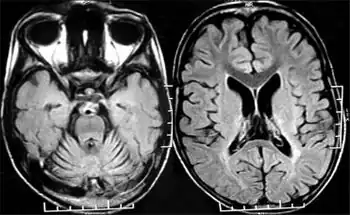

| MRI of cranium revealed cerebellar atrophy out of proportion to the cerebral atrophy | |